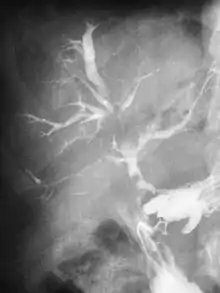

| Abdominal CT scan with right colocutaneous fistula and associated subcutaneous pneumatosis | |